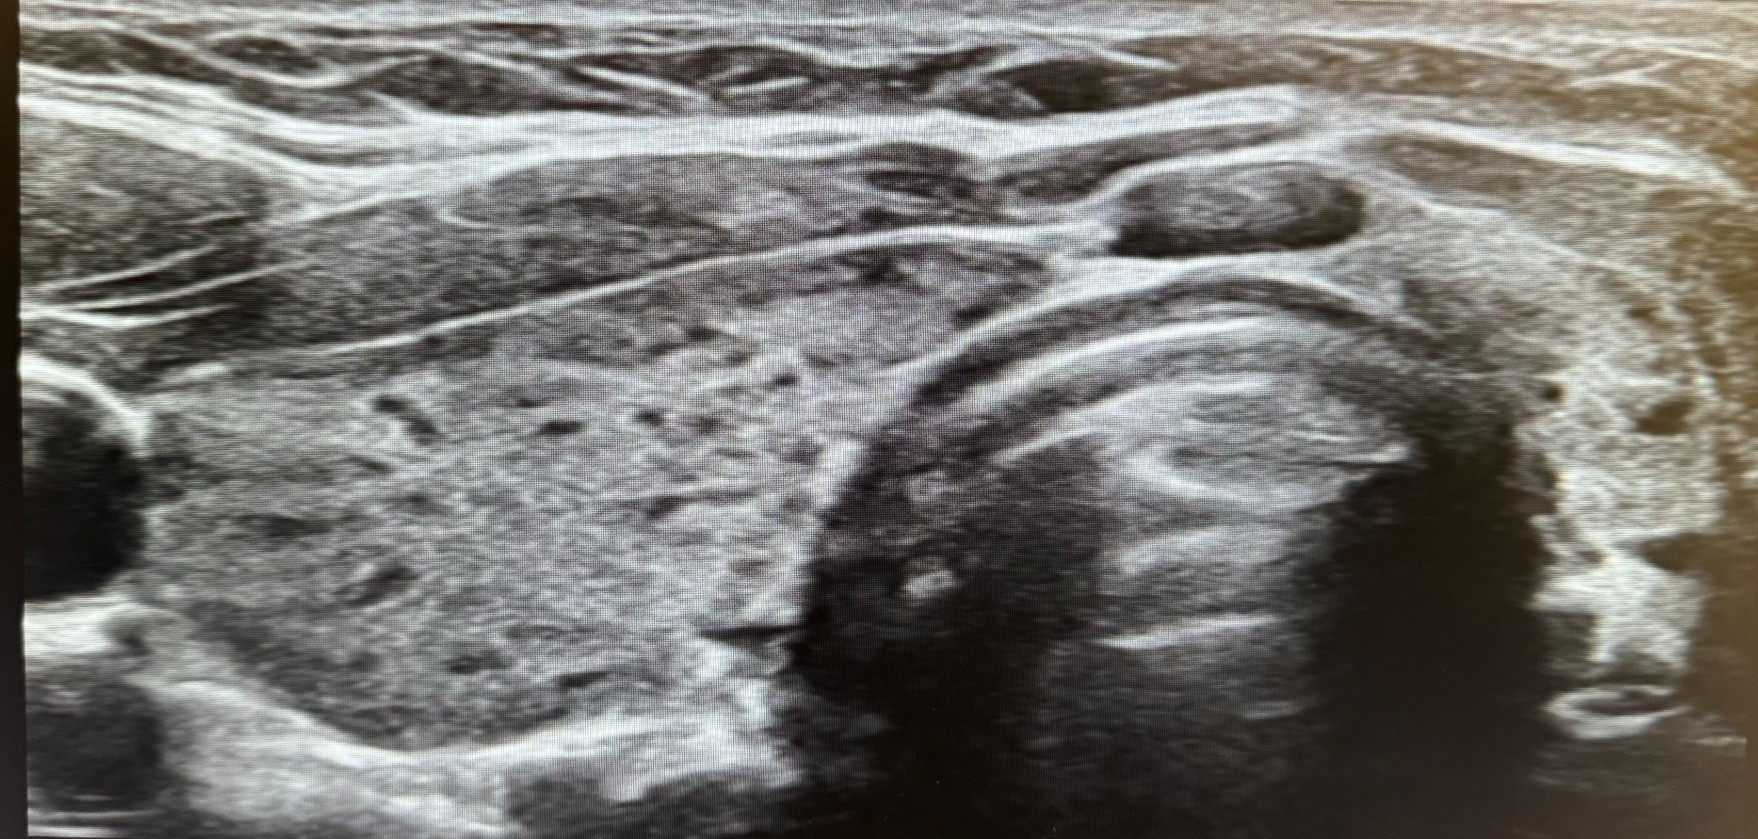

Hallazgos ecográficos

Se realiza una ecografía clínica en la que se objetiva un parénquima tiroideo de aspecto apolillado, heterogéneo con micronódulos hipoecoicos y aumento heterogéneo de la vascularización. No se identifican lesiones nodulares sospechosas de malignidad. Ambos lóbulos tiroideos e istmo presentan un tamaño dentro de la normalidad.

Estos hallazgos ecográficos, junto con la anamnesis y exploración física, orientan al diagnóstico de tiroiditis de Hashimoto.